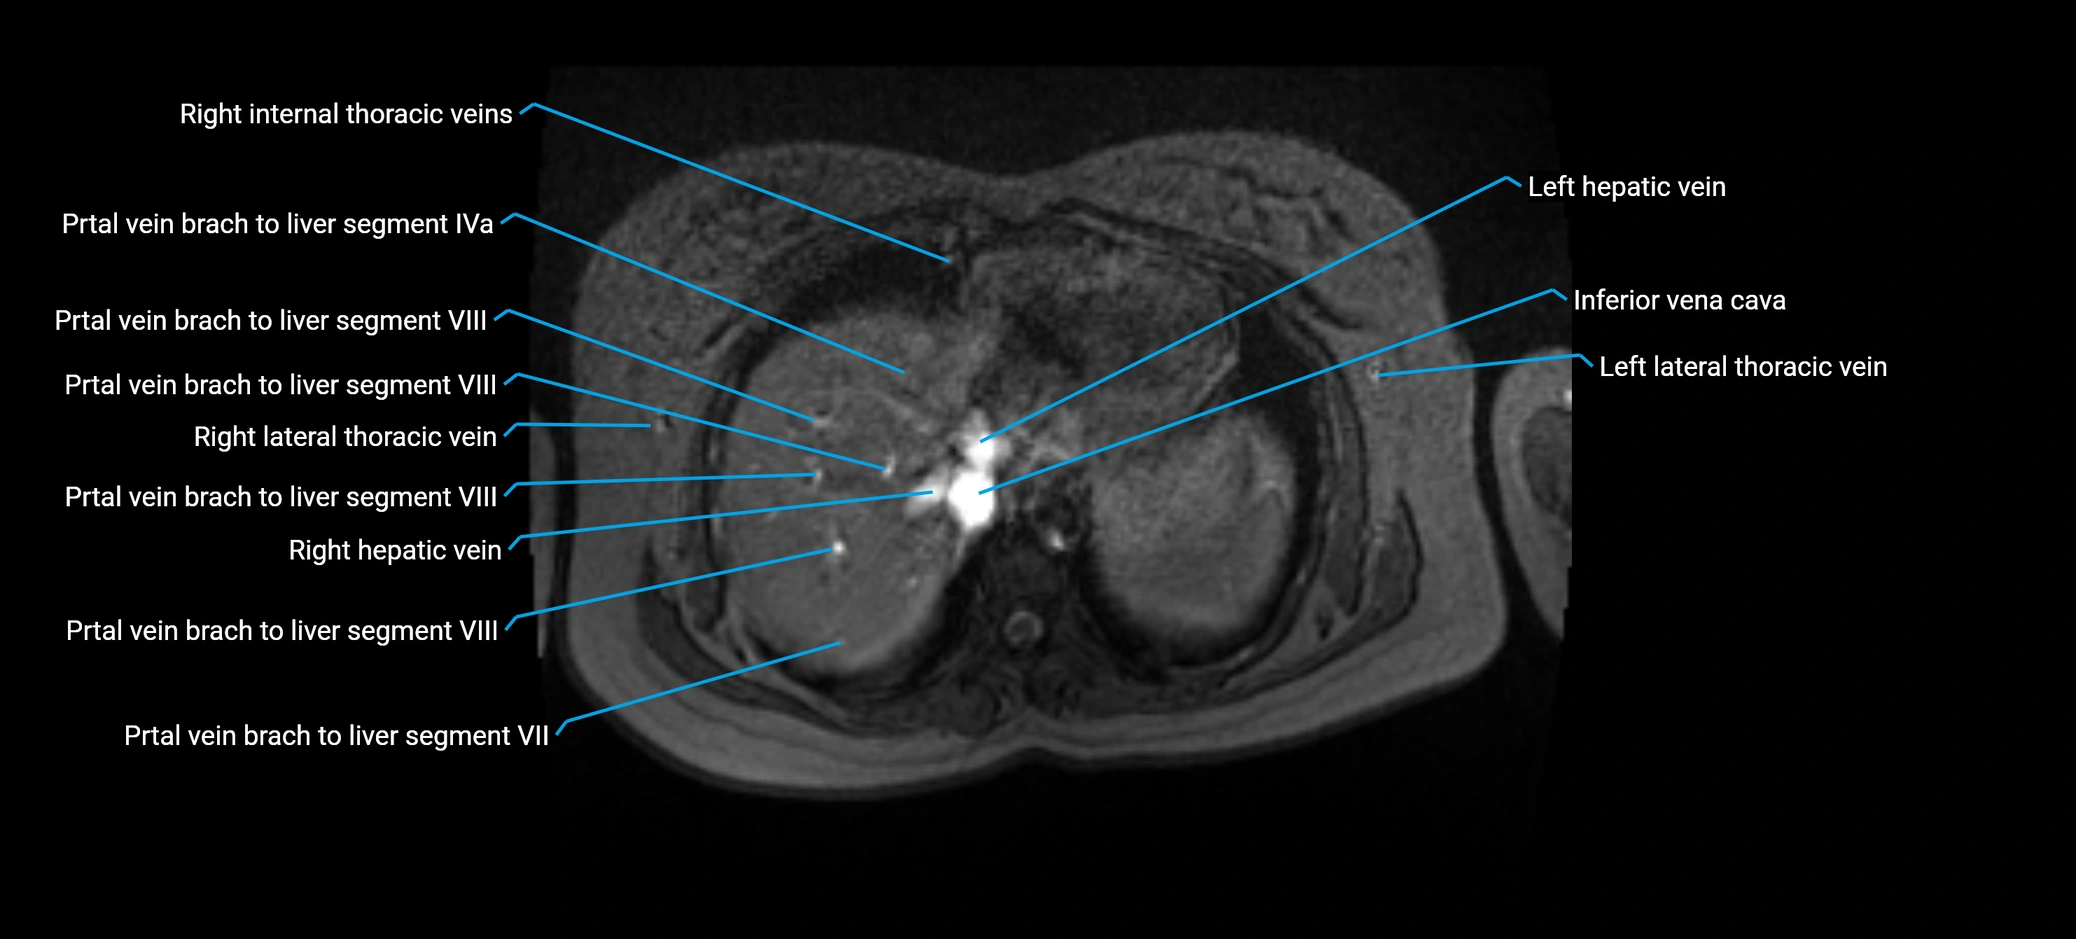

MRV TOF (Time-of-Flight MR Venography):

• Appears as a bright, high-signal vascular channel representing flowing blood

• Clearly shows branching pattern of right portal vein into anterior and posterior branches

• Best in coronal or axial reconstructions for segmental mapping

• No need for contrast, relies on flow-related enhancement

MRI image

image